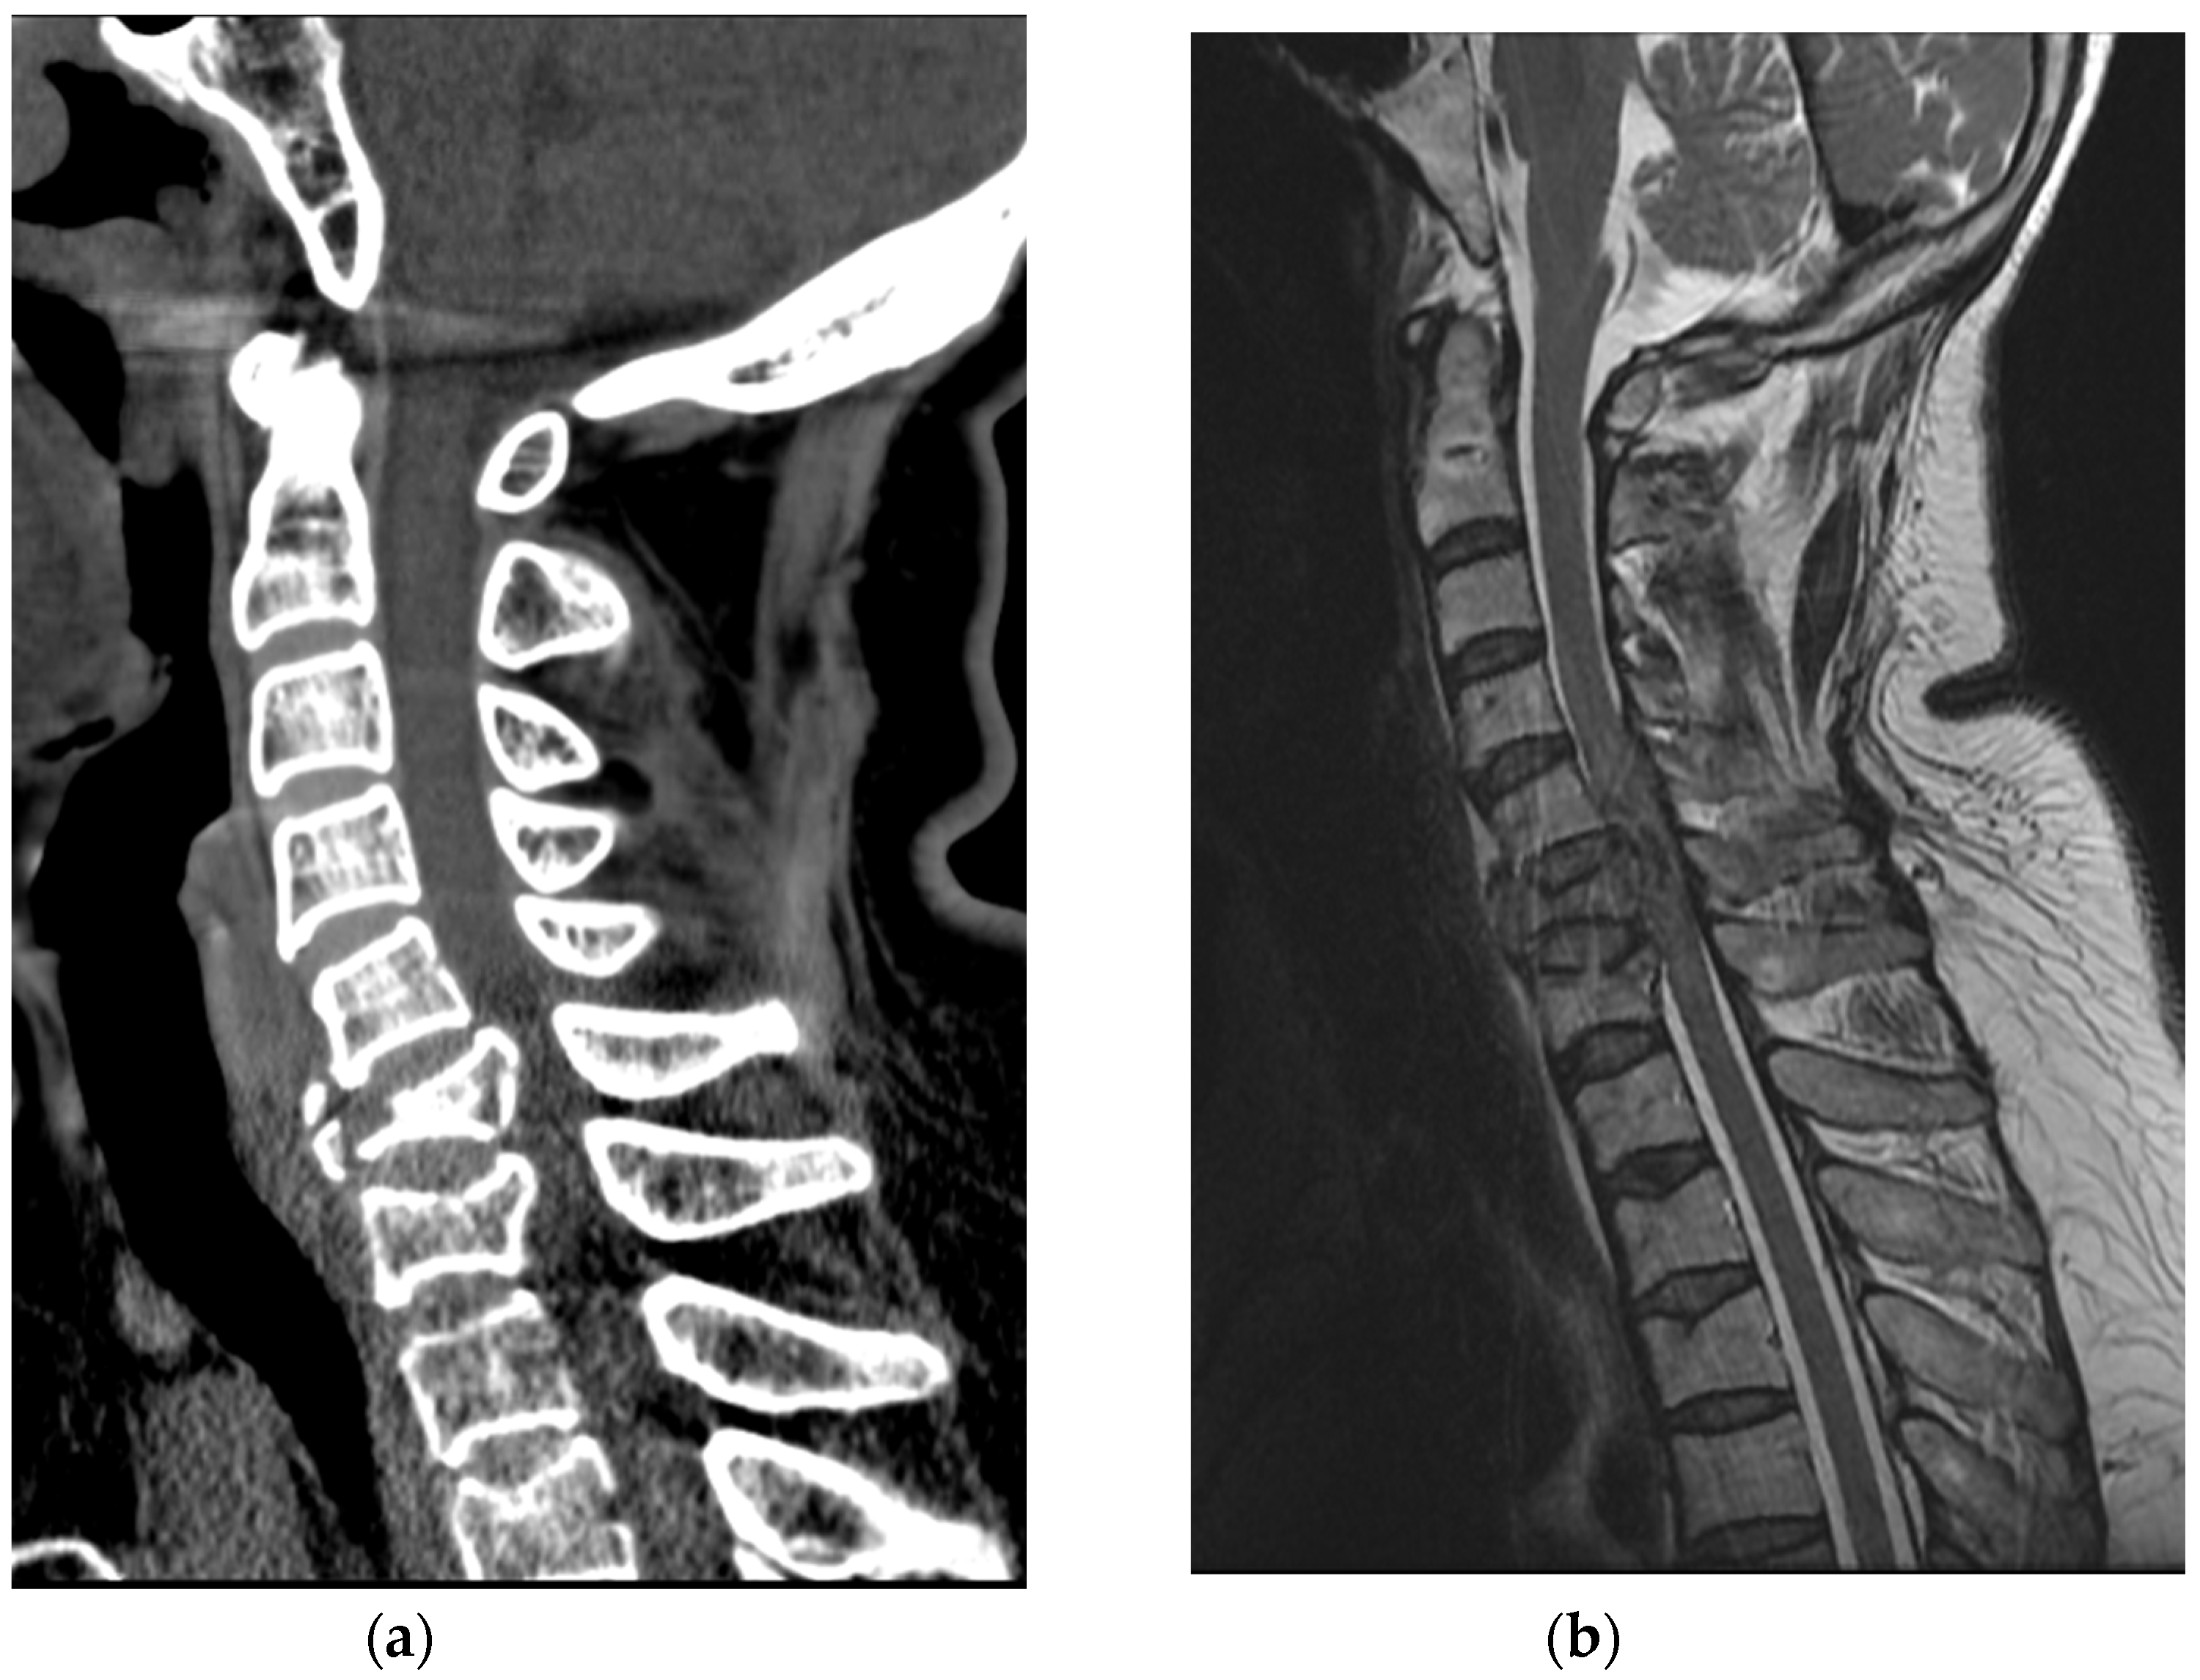

A 63-year-old healthy woman went to a nearby public health center with public outdoor exercise equipment on 23 March 2018. She had undergone right total mastectomy due to breast cancer in 2000 and had been active and capable of performing daily living activities before the accident. At the public health center, she tried the inversion table. Hanging on the inversion table upside down, her feet slipped out of her shoes, and she fell and hit her head on the ground. The patient collapsed and immediately experienced a total loss of motor power in whole body; she was found and transferred to the emergency room of a local medical center. Non-enhanced brain CT did not reveal any abnormalities. Cervical spine CT revealed dislocation of C5-C6 (Figure 5a). For emergent surgical management, the patient was transferred to our hospital. Cervical spine MRI revealed flexion distraction with translation injury at C5-6, leading to C5-6-7 cord contusion with an intramedullary hemorrhage and complete DLC disruption. (Figure 5b).

Figure 5. (a) Cervical spine CT showed C5-C6 dislocation with C6 vertebral body compression fracture; (b) Cervical spine MRI revealed flexion-distraction with translation injury at C5-C6, cord contusion with an intramedullary hemorrhage and complete DLC disruption.